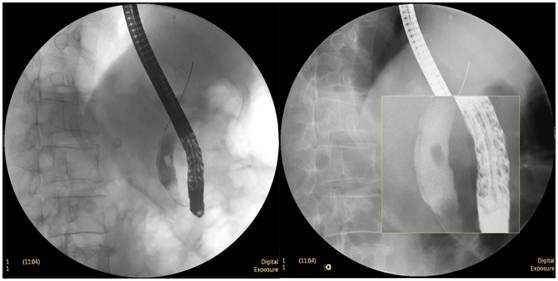

食管惡性腫瘤

食管癌并狹窄內鏡下擴張支架植入術,支架在脊柱背景下依然能清晰顯示。